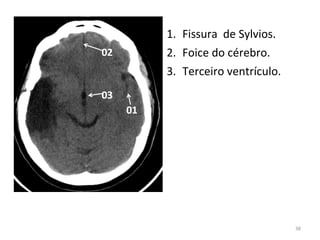

1. Fissura de Sylvios.

2. Foice do cérebro.

3. Terceiro ventrículo.